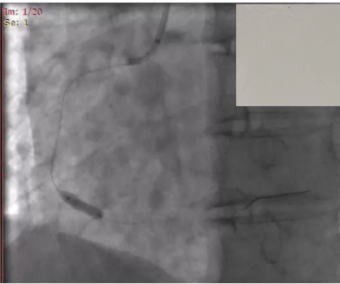

(6) 冠脉造影:左侧冠脉病变严重,行PCI术植入支架。

image.png